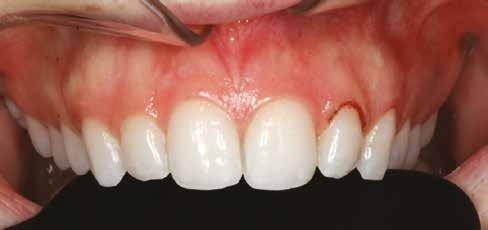

nak megfelelően – előkészítjük (orthofoszforsavval történő savazás, lemosás, szárítás és bond réteggel történő fedés). Ezzel egyidejűleg a ragasztásra kerülő héjak is előkészítésre kerülnek (hidrofolysavval történő savazás, lemosás, szárítás, szilanizálás, bond réteggel történő fedés, és végül az alkalmazni kívánt ragasztóanyag felvitele). Ezután a héjakat a fogak felszínén egyesével pozicionáljuk, majd néhány másodpercen keresztül polimerizációs lámpa segítségével megvilágítjuk. Ezt követően a kifolyó ragasztófelesleget eltávolítjuk, majd elvégezzük a restaurátumok végső polimerizálását. A héjak végleges rögzítését követően az esetlegesen visszamaradt ragasztómaradványok eltávolításra kerülnek, valamint ellenőrizzük az okklúzió és artikuláció közben létrejövő fogérintkezéseket. Az optimális esztétikai eredmény biztosítása érdekében kiemelt jelentősége van a papillák helyreállításának (rózsaszín esztétika). A modern fogorvoslás egyik kiemelt célja a fehér- és rózsaszín esztétika közti harmonikus egyensúly megteremtése. A papillák színe, nagysága és szimmetrikus megjelenése meghatározó szerepet tölt be a rózsaszín esztétika kialakításában. Az íny lefutása ugyancsak rendkívül jelentős mértékben befolyásolja a páciens fogazatának esztétikus megjelenését.

A cikkünkben bemutatásra kerülő eset ellátása során preparációt nem igénylő héjak készítése mellett döntöttünk. A héjak készre vitele során a platinafólia technikát alkalmaztuk. Annak ellenére, hogy az elkészítésre kerülő héjak rendkívül vékonyak, és ezáltal a végleges rögzítésük előtt jelentős törésveszéllyel állunk szemben, összességében mégis olyan minimál invazív kezelési eljárásnak számítanak, amely segítségével kifogástalan esztétikai eredményeket lehet elérni. A fent leírtak alapján bátran javasoljuk e módszer alkalmazását.